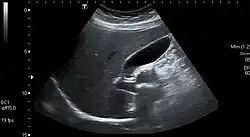

Gallstones form when the bile is saturated, usually with either cholesterol or bilirubin.[20] Most gallstones do not cause symptoms, with stones either remaining in the gallbladder or passed along the biliary system.[21] When symptoms occur, severe "colicky" pain is often experienced in the upper right quadrant of the abdomen.[20] If the stone blocks the gallbladder, inflammation known as cholecystitis may result. If the stone lodges in the biliary system, jaundice may occur; if the stone blocks the pancreatic duct, pancreatitis may occur.[21]

Gallstones are diagnosed using ultrasound.[20] When a symptomatic gallstone occurs, it is often managed by waiting for it to be passed naturally; however, given the likelihood of recurrent gallstones, surgery to remove the gallbladder is often considered.[21] Some medication, such as ursodeoxycholic acid, may be used; lithotripsy, a non-invasive mechanical procedure used to break down the stones, may also be used.[21]

An ultrasound scan is often the first medical imaging test performed when gallbladder disease, such as gallstones, is suspected.[21] An abdominal X-ray or CT scan is another form of imaging that may be used to examine the gallbladder and surrounding organs.[21] Other imaging options include MRCP (magnetic resonance cholangiopancreatography), ERCP (endoscopic retrograde cholangiopancreatography), and percutaneous or intraoperative cholangiography.[21] A cholescintigraphy scan is a nuclear imaging procedure used to assess the condition of the gallbladder.[28]